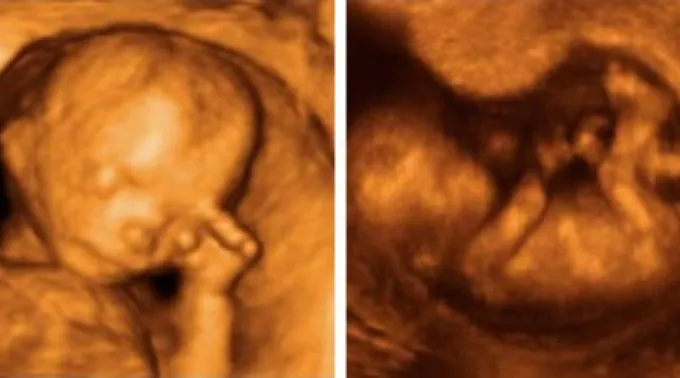

Para realizar a pesquisa, os cientistas britânicos utilizaram ecografias em 4D, com as que observaram 15 bebês e gravaram 342 ocasiões nas quais se tocaram o rosto.

As imagens foram captadas em quatro etapas diferentes da gravidez, entre a 24ª e 36ª semanas.